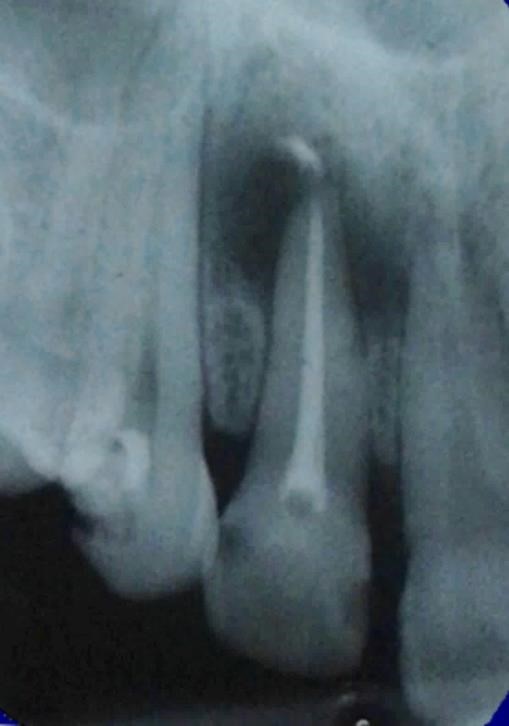

A medicação intracanal foi renovada mensalmente por um período de 3 meses, com o objetivo de determinar a regressão da lesão periapical. Constatando ausência de desconforto, a obturação do sistema de canais, com cimento endodôntico AH Plus (Dentsply) juntamente com a técnica de condensação lateral, a restauração definitiva e em seguida foi realizada do elemento dentário foi realizada com Resina Composta (Opallis- FGM). (Figura 3). Observa-se também nessa radiografia a presença da pasta de Hodróxido de cálcio extravasada , o que determinou a regressão da lesão peripical mais rápida.

Na consulta de proservação, após seis meses da obturação do canal radicular, foi realizado o exame clínico e radiográfico, demonstrando o reparo da lesão periapical (Figura 4).

Figura 3. Obturação do sistem de canais radiculares.

Figura 4. Regressão da lesão periapical.

Observa-se nessa radiografia a formação completa do osso medular com o reparo bem sucedido. Nota também que houve a necessidade da terapia endodôntica do dente 11 devido a mortificação pulpar. Esse tratamento foi realizado em duas sessões, uma vez que a lesão periapical não era extensa como no dente 12.